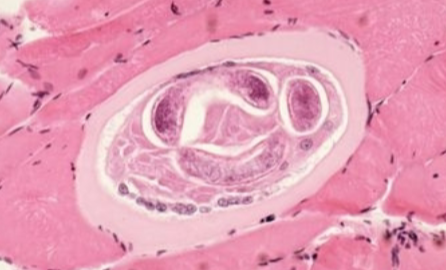

Trichinella spiralis